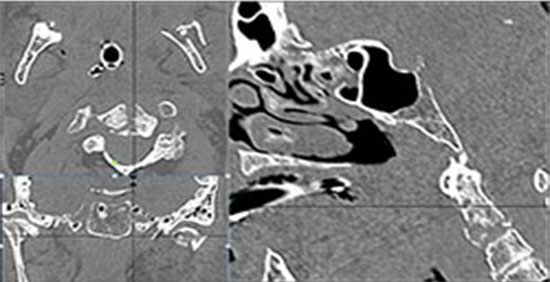

The medial, lateral and posterior maxillary walls are fractured. |

Yes | NA |

The infraorbital rims and orbital process of the zygoma and/or frontozygomatic suture are fractured. |

The alveolar ridge, premaxilla, and/or the palatine process of the maxillary bones on either side are fractured. |

The pterygoid processes of the sphenoid bone are fractured. |

The the zygomatic arch, frontozygomatic suture or infraorbital rim are fractured. |

The lateral wall of the orbit is fractured. |

LeFort type III, orbital zygomatic and orbital floor and fronto - naso-ethmoidal complex fractures with possible injury optic nerve/sheath - extent described above.